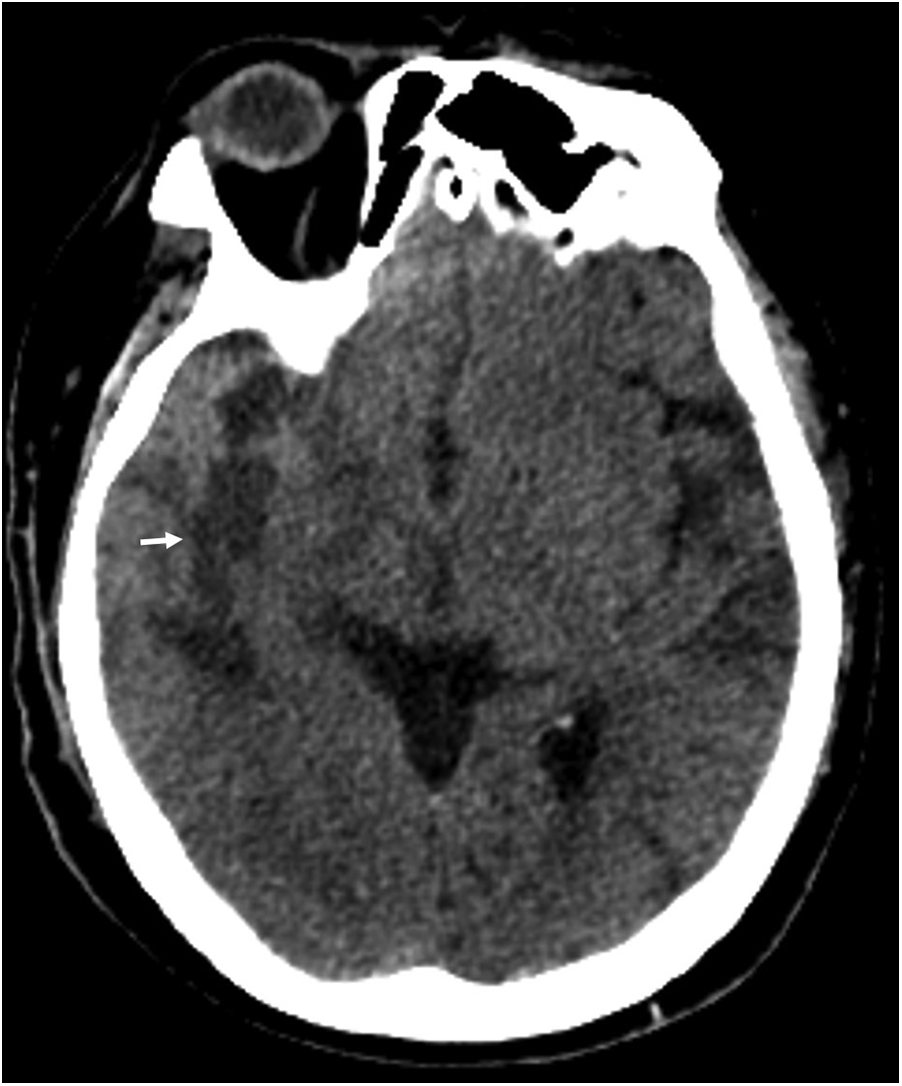

A 58-year-old male with a medical history of hypertension, diabetes and gastro-oesophageal junction low-differentiated invasive adenocarcinoma. Preoperative transthoracic echocardiography revealed a mild degree of heart chambers with a 2 mm PFO and valvular function was normal. Electrocardiogram demonstrated AF and ventricular premature beats. On October 26, 2021, a TIVAP was implanted in the patient's right chest wall for chemotherapy, with the tip positioned at the junction of the superior vena cava (SVC) and the right atrium under fluoroscopy. The patient received six cycles of systemic chemotherapy, comprising intravenous oxaliplatin 100 mg/m2 on day 1, oral S-1 80 mg twice daily for 14 days every three weeks. Although the patient has completed the last intravenous chemotherapy in July 2022, the TIVAP was not removed for concern about recurrence. Regular TIVAP maintenance was performed through noncoring needle with 0.9% sodium chloride every four weeks, and the tumor showed complete remission during follow-up. On February 11, 2024, the patient presented to the emergency department with dizziness and left limb weakness lasting two days. Physical examination revealed left nasolabial fold flattening, rightward deviation of the jaw upon mouth opening, and inaccuracy in the left finger nose test. Cranial CT indicated a right temporal lobe infarction (Figure 1). Symptoms improved following the treatment of clopidogrel 75 mg and atorvastatin 20 mg daily. Ultrasound examination showed no abnormalities in the carotid and vertebral arteries, and no thrombosis in the deep and superficial veins of the lower limbs. Transesophageal echocardiography revealed a 44 mm × 23 mm mass in the right atrium and a 2 mm PFO. Further cardiac CT confirmed the mass at the entrance of the SVC into the right atrium, with normal left heart and pulmonary arteries (Figure 2). Differential diagnosis included atrial myxoma, thrombosis, metastatic tumors and infective endocarditis-related vegetations. Two weeks after anticoagulation with vitamin K antagonists, the mass remained static. The TIVAP was used for administering therapy for normal function during this stage. On March 21, 2024, the patient underwent right heart mass resection, PFO repair, TIVAP removal and left atrial appendectomy for reducing the risk of thrombosis in the future. Postoperative pathology showed fibrous tissue without proliferative cells, revealed that the mass was thrombosis (Figure 3). The patient recovered well and was discharged, with no embolic events during follow-up on continuous rivaroxaban 20 mg daily.

Figure 1

Cranial CT showed right temporal lobe infarction (white arrow).